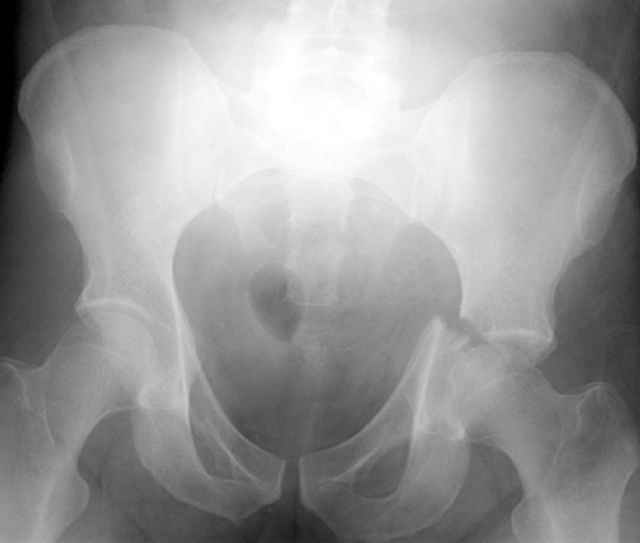

For Alex... here are some cannulated and 7mm screws for you... notice the fracture malreduction as indicated by the head subluxation on both views...this was a percutaneous technique without open reduction... I don¹t like it but there it is... the fixation technique is not at fault, because there was no open reduction of the fracture... but let¹s not get in to all that.